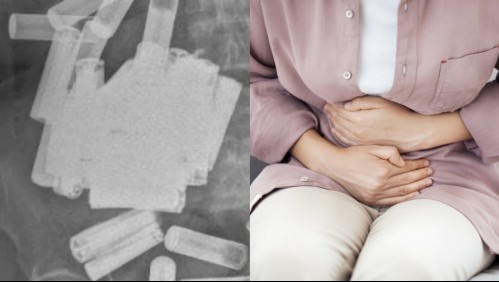

Mundo Fue al doctor por dolores abdominales y le terminaron extrayendo 55 pilas de su estómago e intestino